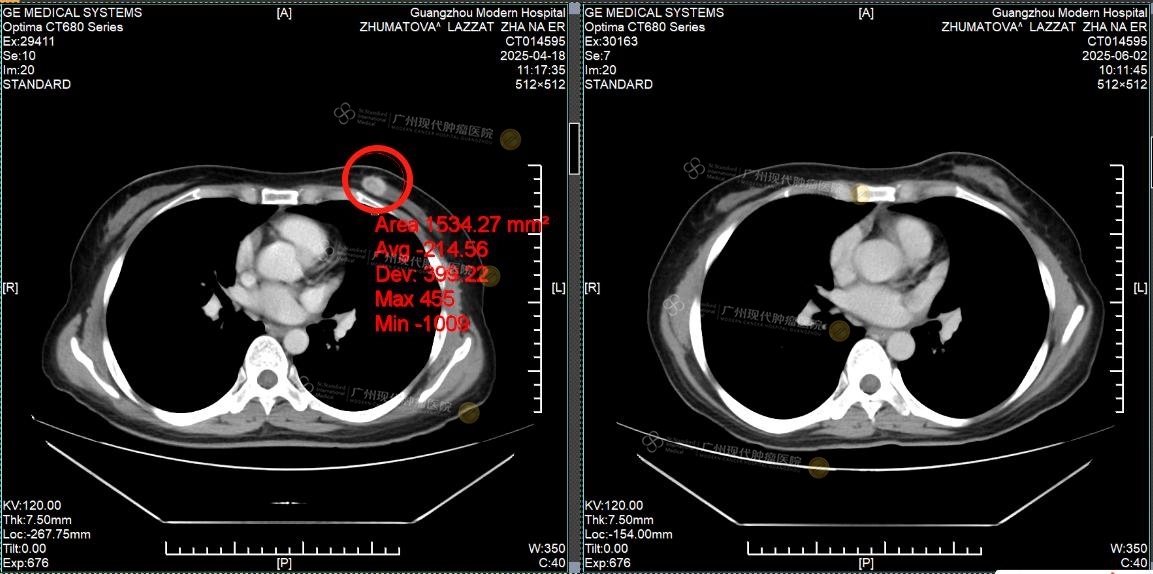

Pada April 2025, Lazzat datang ke rumah sakit kami ditemani oleh kakaknya dan menjalani pemeriksaan menyeluruh. Hasil CT menunjukkan bahwa terdapat massa tumor pada payudara kiri dengan ukuran sekitar 2×1cm, serta banyak lesi metastasis di hati, dengan diameter nodul terbesar lebih dari 4cm. Fungsi hati juga telah terpengaruh oleh tumor.

Tumor payudara: sebelum pengobatan VS sesudah pengobatan

Setelah menjalani 2 siklus pengobatan, tumor payudara Lazzat berhasil dihilangkan sepenuhnya dan tidak terdeteksi lagi saat pemeriksaan ulang. Lesi metastasis di hati menyusut lebih dari setengah, fungsi hati kembali normal, dan penanda tumor seperti CEA dan CA153 menunjukkan penurunan yang signifikan. Berkat perawatan yang cermat dari tenaga medis, fungsi hatinya membaik, rasa lelah dan lemas pun berkurang secara nyata, dan ia kembali merasakan semangat hidup yang sudah lama hilang.